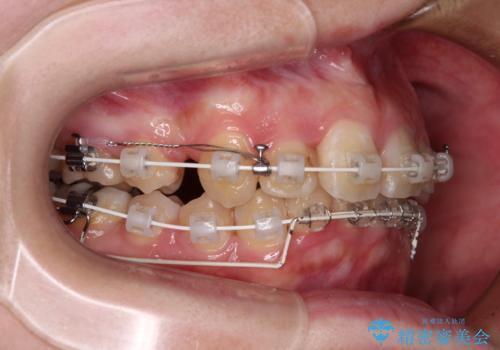

- 矯正装置

- 審美装置

上顎左右第一小臼歯の2本を抜歯し、ワイヤー装置を使用して咬み合わせ高さを改善しながら、歯列を整えて行くこととしました。

事前にむし歯の疑いがある歯があり、処置を行いましたが、矯正治療中に失活してしまい、ワイヤー装置除去後に、根管治療とセラミッククラウンによる補綴治療を行いました。

矯正治療は2年半ほで無事におけることができました。